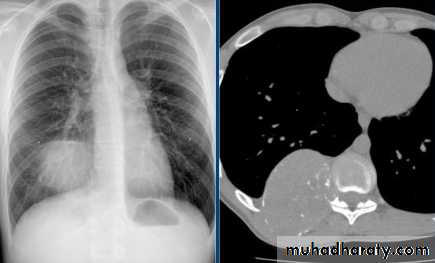

Unilateral rt. Hilar LNE, increase density, lobulated outline.

Identify main lower lobe pulmonary arteries: They can be compared to a little finger pointing downwards and medially. Sometimes, usually on the left side – it can appear only as the proximal phalanx of the finger.Interpretation: If the little finger shadow of the right lower lobe artery is not seen then you must check for evidence suggesting collapse of the right lower lobe.Identify the hilar point: Look for the site where the most superior upper lobe vessel – either vein or artery – crosses the lateral margin of the little finger. The point of crossing is known as hilar point and forms a horizontal “vee” (> or <).Interpretation: The left hilum must never be lower than the right hilum. Whenever a left hilum appears lower than the right hilum – look for other evidence suggestive of: 1- Collapse of either the left lower lobe or of the right upper lobe or 2- Enlargement of the right hilumBilateral hilar LNE